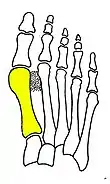

Syndesmosis procedure addresses specifically the two fundamental problems of metatarsus primus varus deformity that gives rise to the bunion deformity. They are leaning and instability of the first metatarsal bone . Syndesmosis procedure uprights the leaning first metatarsal bone with strong binding sutures between it and the second metatarsal bone (Fig. 2) and then also stabilizes it uniquely by creating a fibrous connecting bridge between these two bones (Fig. 3, 4). First metatarsal bone can be readily realigned because by definition of the metatarsus primus varus deformity its first metatarsal is abnormally loose and mobile.